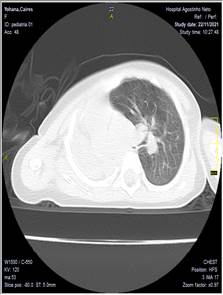

Se realizó una tomografía axial computarizada de tórax evidenciándose hipoplasia pulmonar fig. 1

Se realiza espiral tomográfico axial simple a 5 mm de tórax con reconstrucciones axiales milimétricas, sagitales y coronales en equipo multicorte observándose asimetría de ambos hemitórax, siendo mayor el derecho de aspecto compensador con desplazamiento de las estructuras del mediastino a la izquierda. Pulmón izquierdo pequeño. Presencia de disminución del calibre de los vasos pulmonares, así como el aparato bronquial.

Conclusión. Hipoplasia pulmonar izquierda

Fig. 1. Tomografía axial de tórax. A. corte axial. B. corte coronal. C. corte sagital

Tomografía de tórax: Opacidad homogénea en hemitórax izquierdo con desplazamiento de las estructuras del mediastino, reducción del volumen pulmonar derecho.